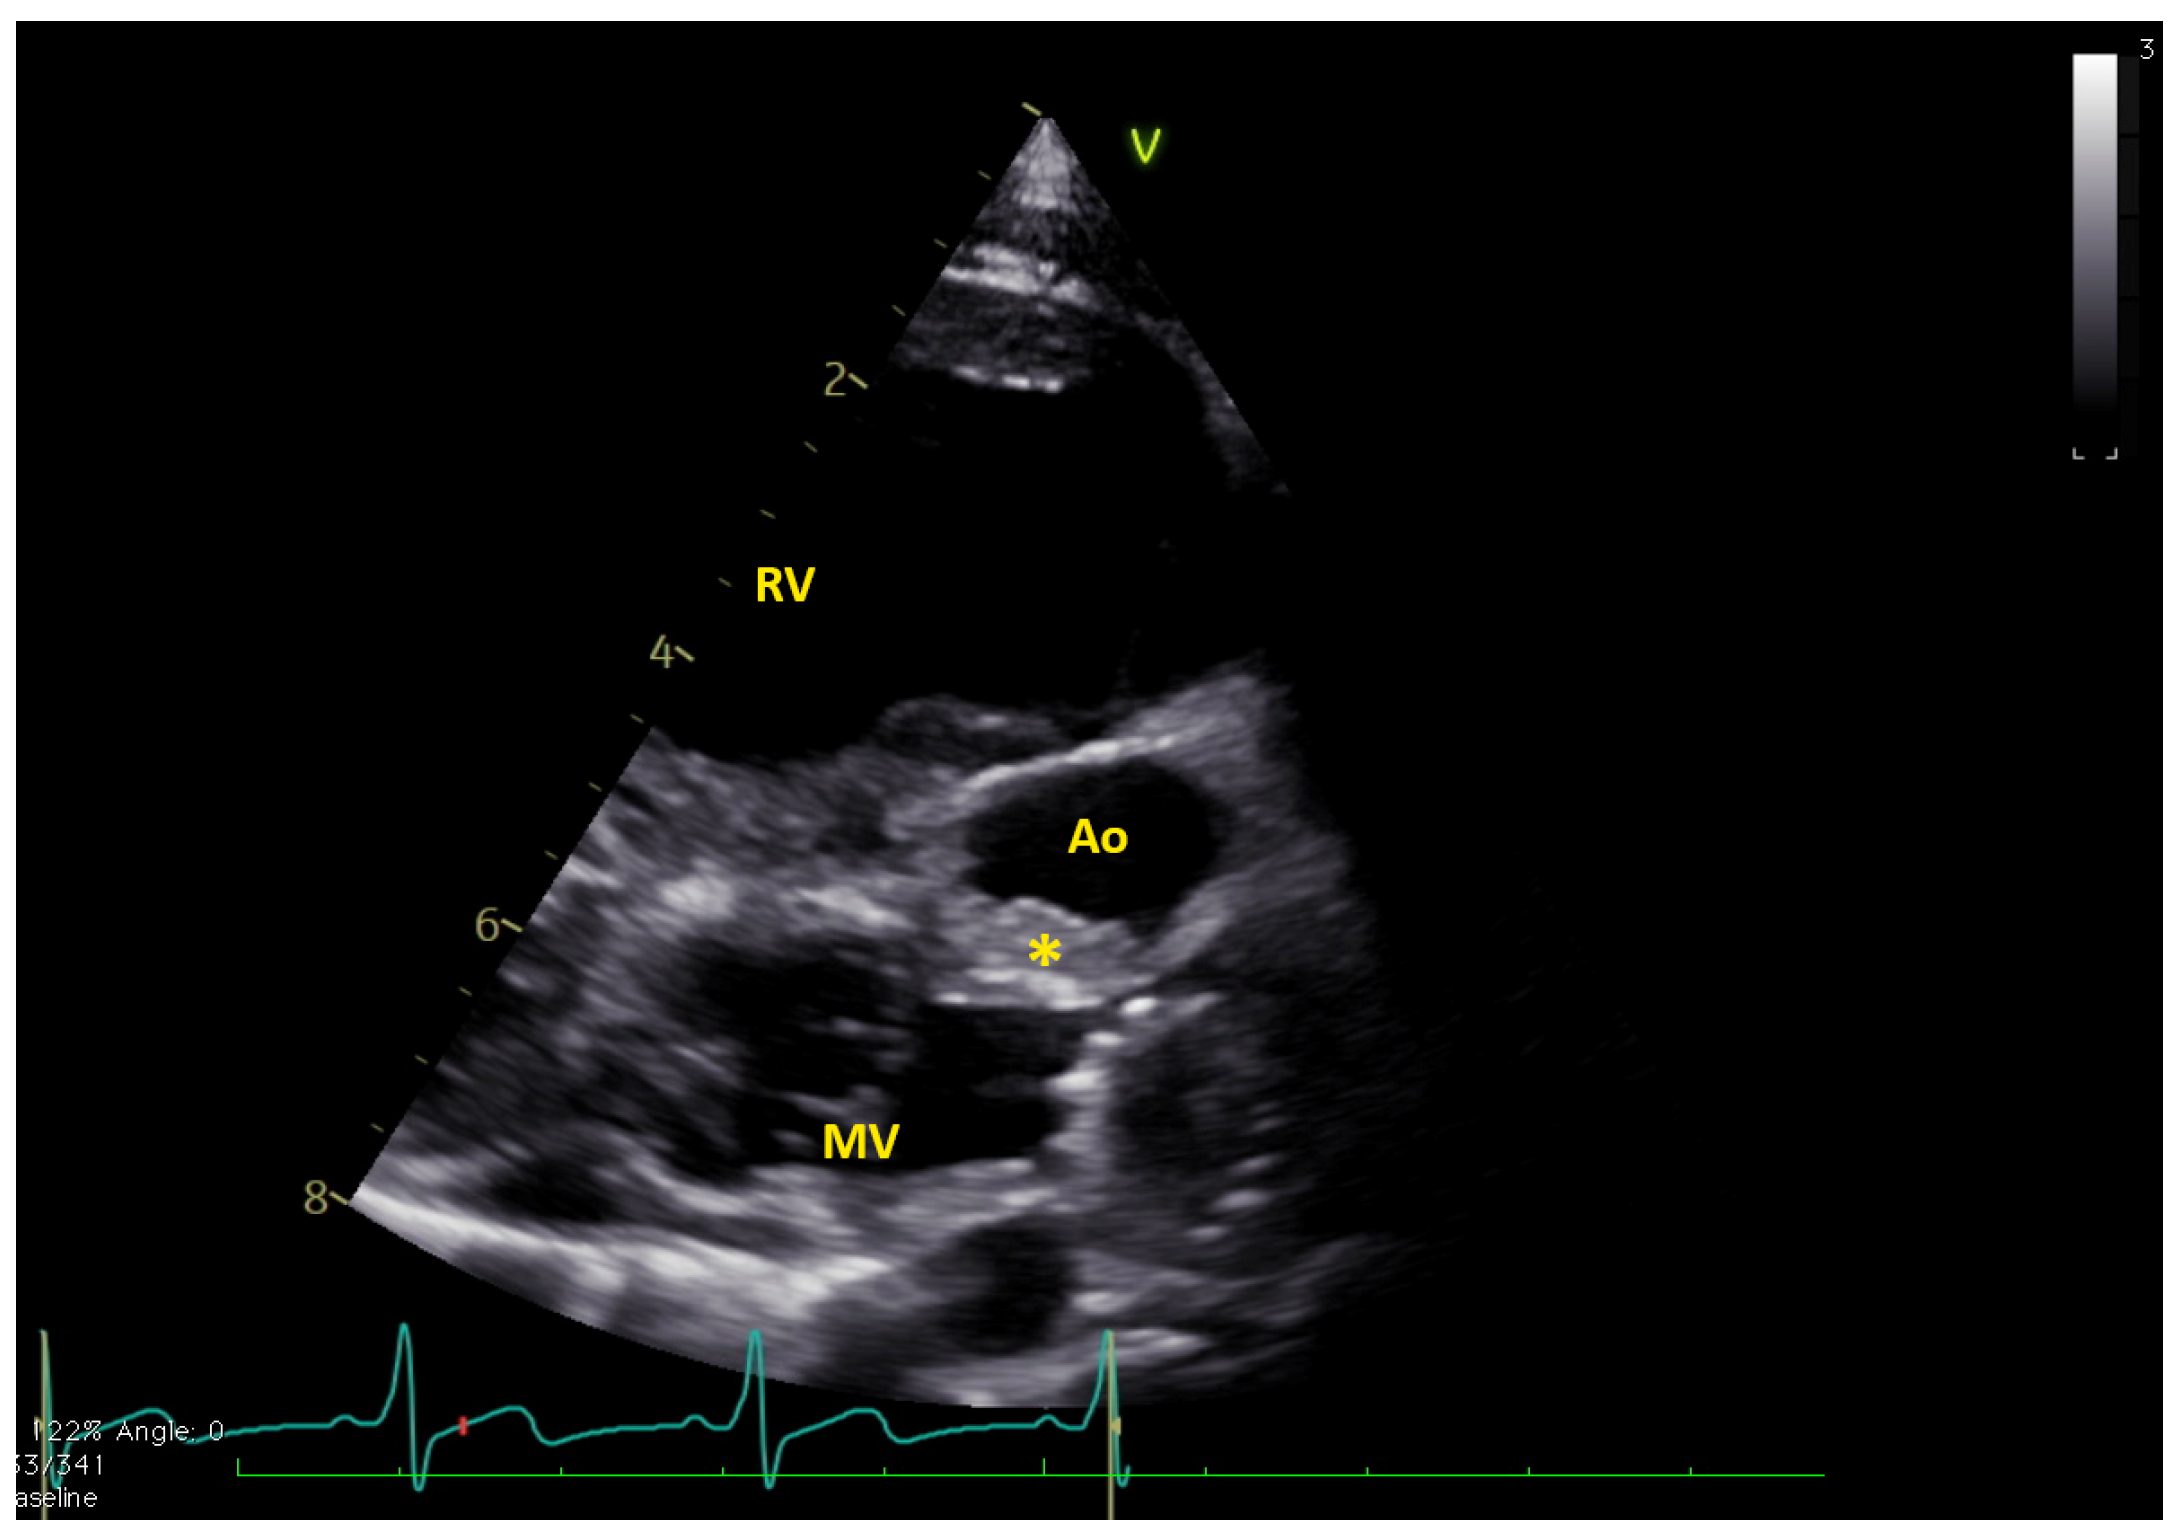

2. Experience